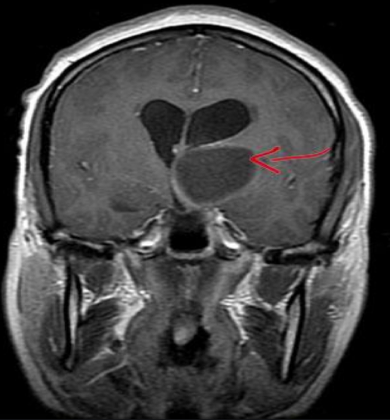

丘脑上长瘤发展快吗?INC国际神经外科专家表示,丘脑上一般不会长肿瘤,如果生长肿瘤,一般以神经胶质瘤为主。而胶质瘤的生长速度和肿瘤分级关系密切,一般分级越高,肿瘤细胞生长也就越快。目前还没有确切的胶质瘤的生长速度的数据。一般来说,低级别胶质瘤,也就是病理报告为1级和2级的胶质瘤,其生长相对缓慢,大约以每年4mm直径的速度生长,部分患者甚至可以常年保持稳定,无明显增大。当然,也有低级别胶质瘤发生恶性转变的可能,这时肿瘤的生长速度就会明显加快。病理分级为3级到4级的高级别胶质瘤的生长速度迅速,并且就和杂草的生长方式是一样的,浸润性生长,可以向四面八方侵蚀周围的神经组织以及其他组织,有的时候甚至一般几周~几个月就可以长得很大,出现严重的颅内压增高等症状,有的患者甚至只能存活3-6个月的时间。

手术是胶质瘤较常见的初始治疗方法。手术过程中进行的活检为病理学家提供了组织样本,病理学家将能够对肿瘤成分做出准确诊断,这对获得更佳治疗至关重要。手术还可以切除肿瘤组织,以缓解肿瘤对大脑造成的压力。但丘脑与神经结构之间有着无数的联系,由于丘脑有无数的网络,它实际上被国际各地的许多研究人员认为是大脑中较“连线”的部分。由于丘脑周围有着各种重要组织,与各种重要组织都有紧要联系,所以手术切除时,还要注意保护丘脑及其周围神经组织不受伤害。加上丘脑位置深在,位于大脑中心,所以手术难度较高,一般的神经外科专家都难以在丘脑上做手术。

丘脑肿瘤在治疗后,CT或核磁共振还可能显示出类似胶质瘤的脑组织。这通常是由于放射治疗、化疗或两者同时引起的死亡组织或健康组织的变化。在治疗后,神经外科医生也将密切关注这一情况,以确定胶质瘤是否复发。